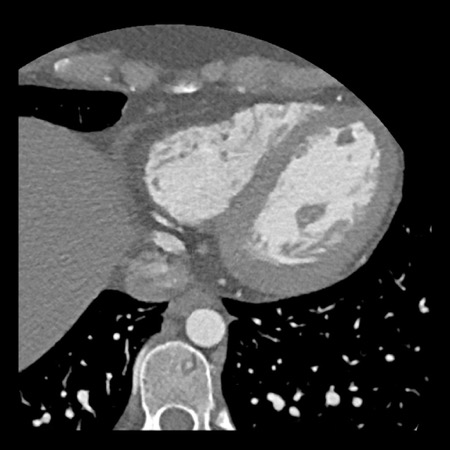

case 1 – CAD-RADS 2/P1

First, scroll through the scan.

Not all images are included. Some images without any abnormalities are skipped

from the series.

How would you describe the findings on the coronary CTA?

The findings are:

- Agatston score of

this patient was 14 (P1). Please, also note the calcification of the aortic valve. - Some partially

calcified and calcified plaques are present in the LAD with mild stenosis

(25-49%). - Calcified-plaque in

the LCX causing minimal stenosis (<25%). - Non-calcified

plaque in the distal RCA causing minimal stenosis (<25%). - This patient classifies

as CAD-RADS 2/P1, which means no further workup is needed.